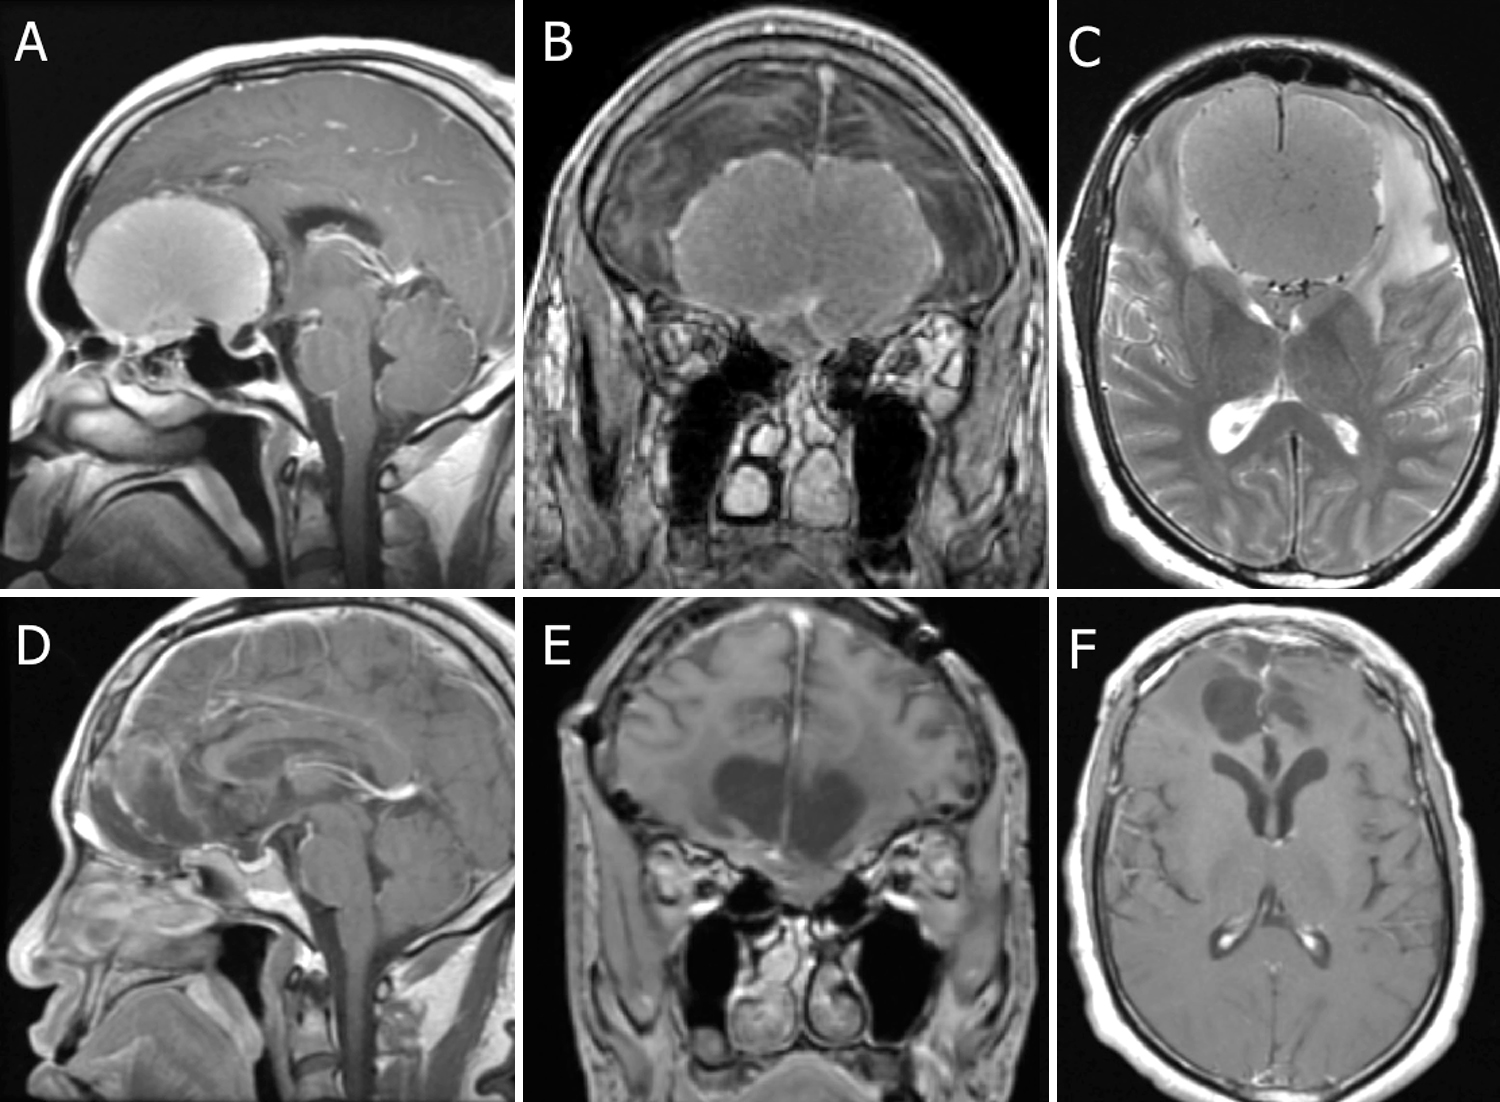

A-C:术前矢状位(A)和冠状位(B)后Gd T1加权和轴向T2加权(C)MR图像显示一个大的、53.3×69.7×69.2-mm的OGM,在眼眶上有明显的侧向延伸,并向前延伸至额窦后部。也有血管受累,没有皮质袖带和相关的脑水肿(C,狮子鬃毛征)。技术法规(辛普森一级)通过跨基底方法实现。D-F:术后Gd T1加权矢状面(D)、冠状面(E)和轴向(F)MR图像显示肿瘤完全切除,无任何残留或复发。